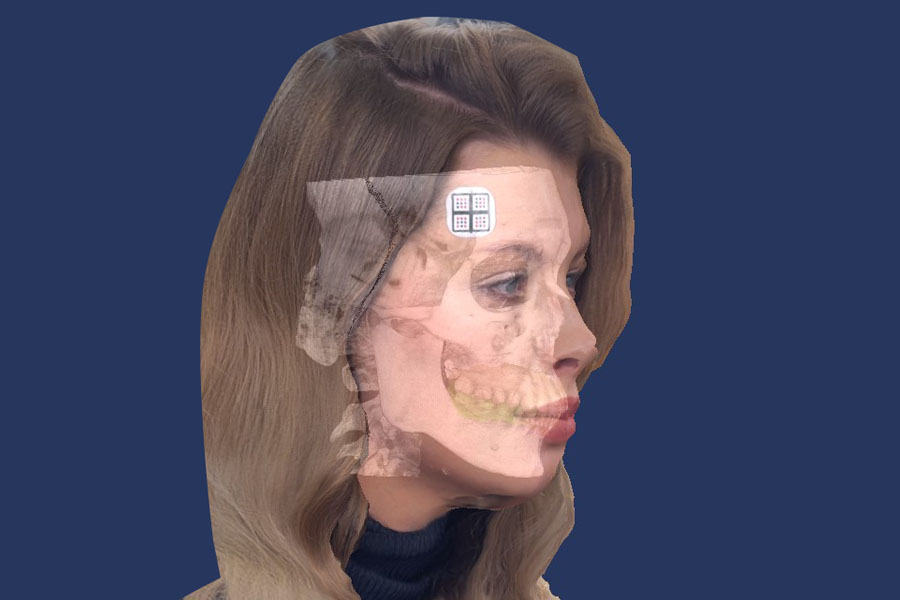

Be sure to try facial scanning

It allows you to analyze aesthetic parameters and align the treatment plan with the patient, considering the new aesthetic guidelines.

Merge all data into one 3D model. See all in real-time animation